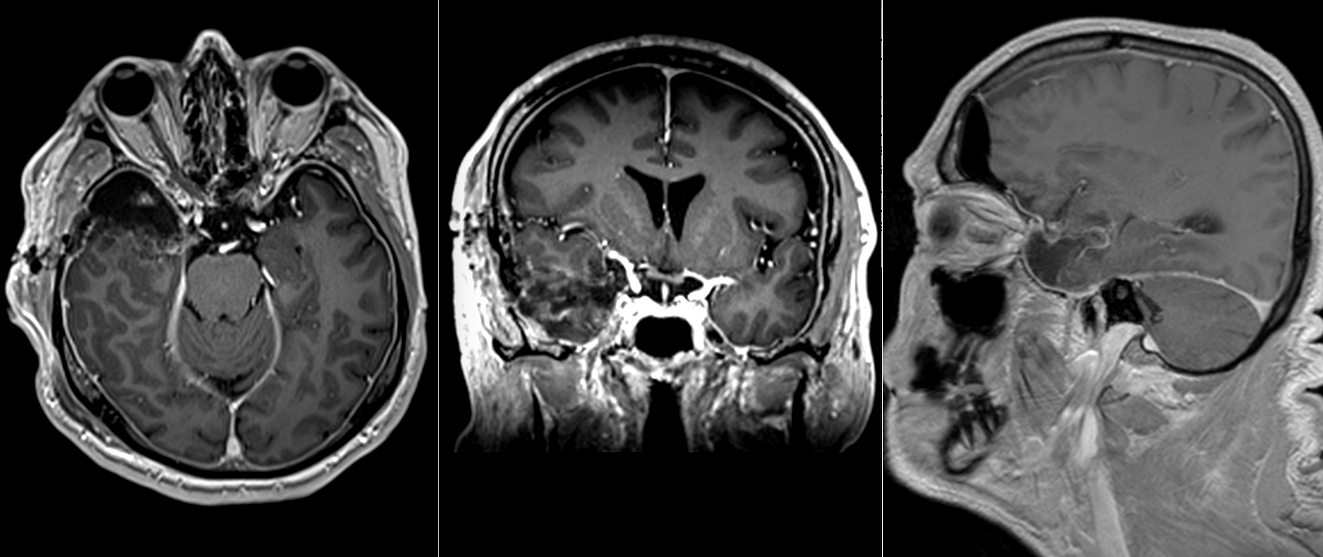

Controlul RMN efectuat la 2 ani după intervenție confirmă rezultatul chirurgical: nu există rest tumoral și nici semne de recidivă.

RMN postoperator la 2 ani